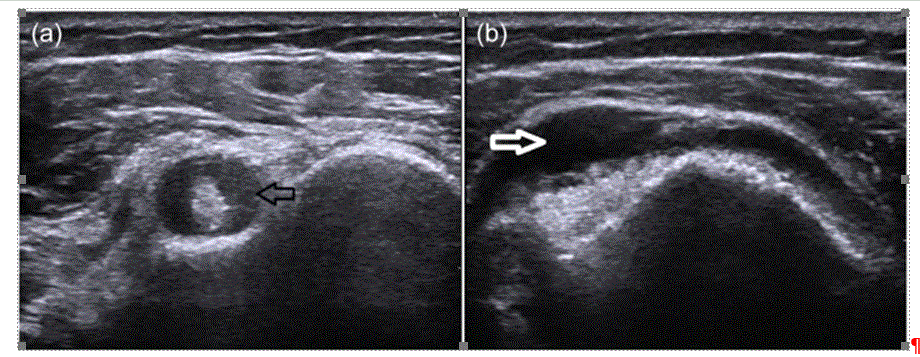

今回、上腕二頭筋健の所見が綺麗に見えました。

ここにエコーを当てると下記上図a のようなエコー画像が綺麗に見えました。

健周囲にfluid貯留が見えます。。

他には三角筋下の滑液包炎もエコーで上図bのように見えるようです。

ひとまず、上腕二頭筋健のエコーはとても簡単なので、PMRを疑えばひとまず行うのは良いと思いました。